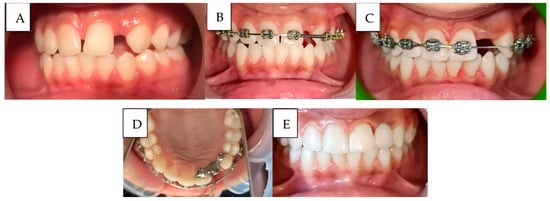

Case 1 (Figure 4):

A 14-year-old adolescent presented to the Department of Pediatric Dentistry 18 months after a traumatic dental injury. The trauma had resulted in complete avulsion of tooth #21, accompanied by space loss due to the drift of teeth #11 and #22 into the edentulous area. The case was managed using a fixed orthodontic appliance to regain the lost space, followed by prosthetic rehabilitation with an adhesive bridge to replace the missing tooth. The overall treatment duration was seven months.

Figure 4. A case of anterior teeth axis correction using fixed orthodontic treatment to redistribute the space of a missing lateral incisor, followed by replacement with an adhesive bridge: (A): Before treatment, (B): After appliance placement, (C): Completion of orthodontic treatment, (D): Adhesive bridge application, and (E): The final result, showing the bonded bridge in place from the frontal view.